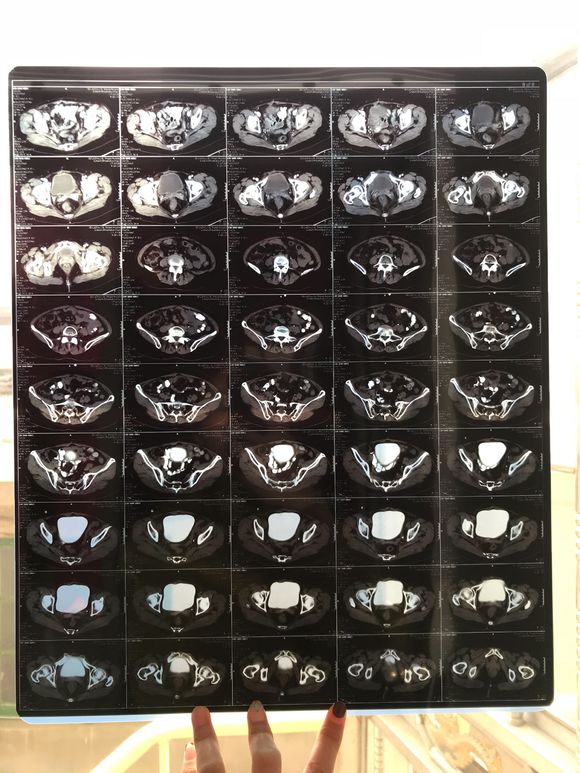

和你的故事 02019-04-09 患者家属我妈妈的病理结果报告,3期c1,大家可以帮忙看看吗,跪求了!我很急,谢谢!想知道是否严重,目前等术后出院后去肿瘤医院...

0人关注 4个回复 3491次浏览 -